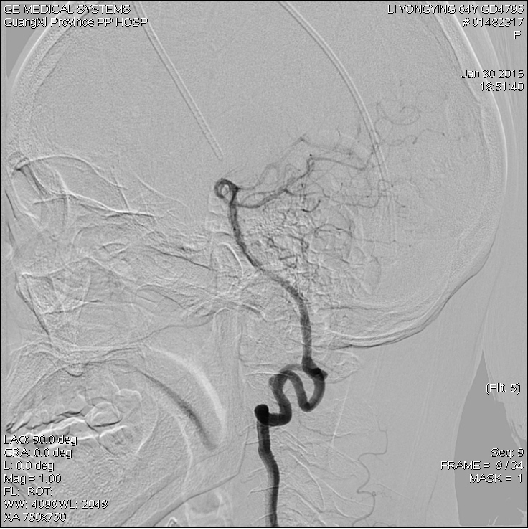

2015-1-30 DSA